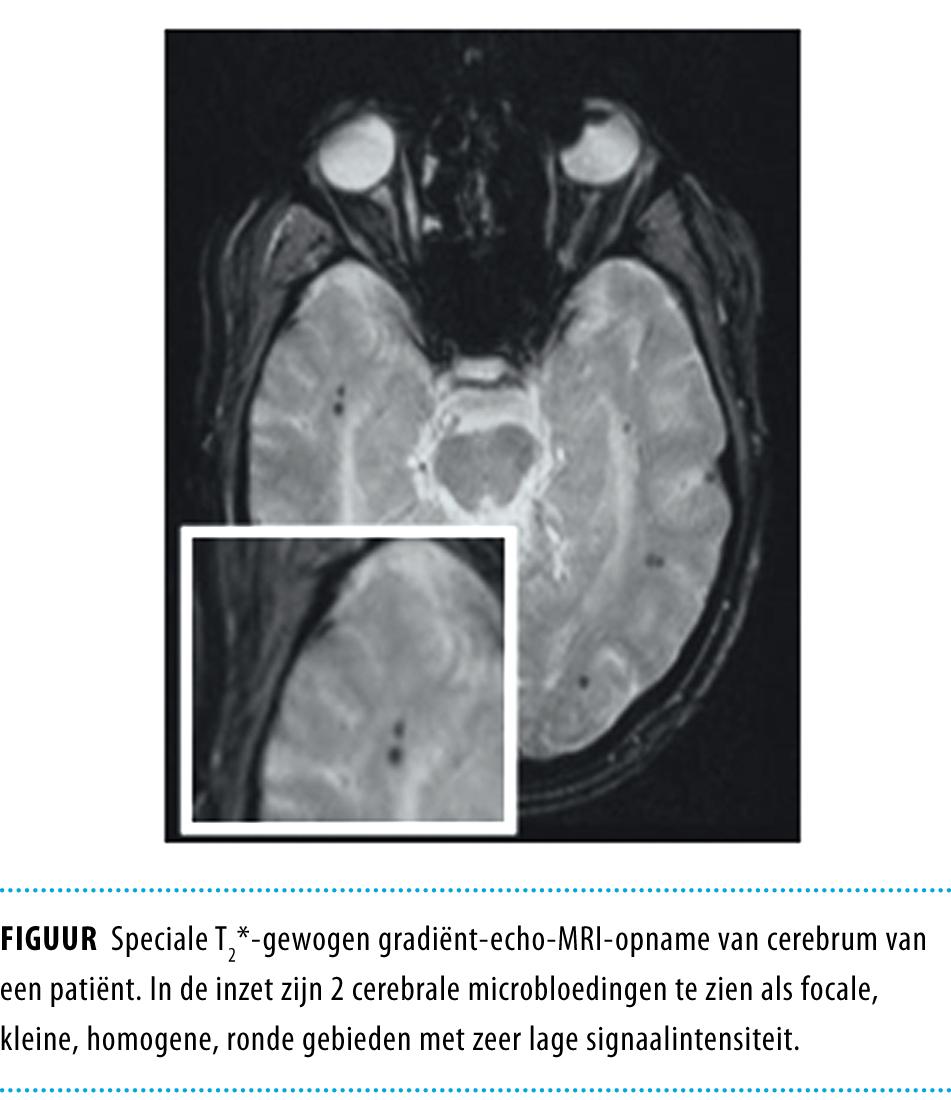

Bij 500 niet-demente ouderen met bekende CSVD werden de aanwezigheid, het aantal en de locatie van microbloedingen beoordeeld op T2*-gewogen gradiënt-echo-MRI-opnames. We bepaalden het cognitief functioneren met verschillende testen. In de statistische analyses corrigeerden we voor verschillen in leeftijd, geslacht, opleidingsniveau, depressieve symptomen, totaal hersenvolume, volume van de wittestofafwijkingen, en aantal lacunaire en territoriale herseninfarcten.

De gemiddelde leeftijd was 65,6 jaar (SD: 8,8) en 57% van de patiënten was man. 52 patiënten (10,4%) hadden microbloedingen. Patiënten met microbloedingen waren significant ouder, hadden een groter volume wittestofafwijkingen en meer lacunaire infarcten (alle p < 0,001). De aanwezigheid en het aantal microbloedingen waren gerelateerd aan een slechtere globale cognitieve functie, tragere psychomotorische snelheid en verminderde aandacht. Microbloedingen in de frontale, temporale en diepe hersengebieden hadden het sterkste verband met cognitief disfunctioneren.